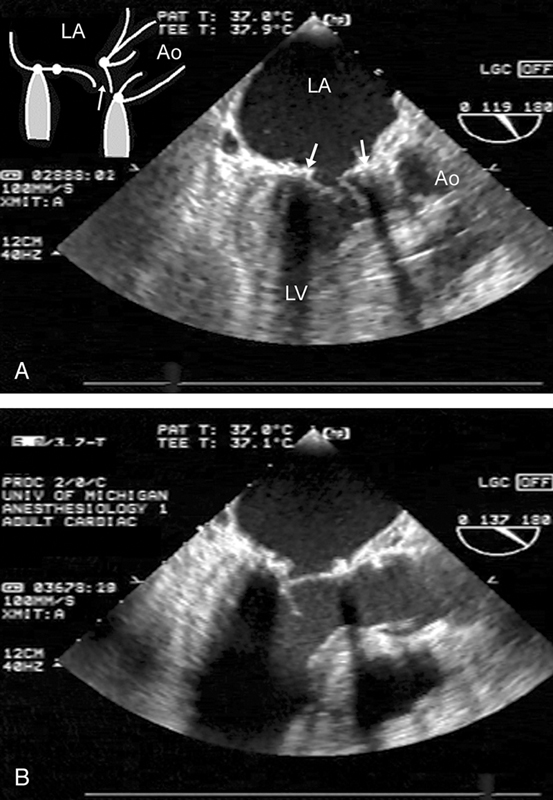

فحوصات تشخيصية لبعض امراض القلب والشرايين التاجية